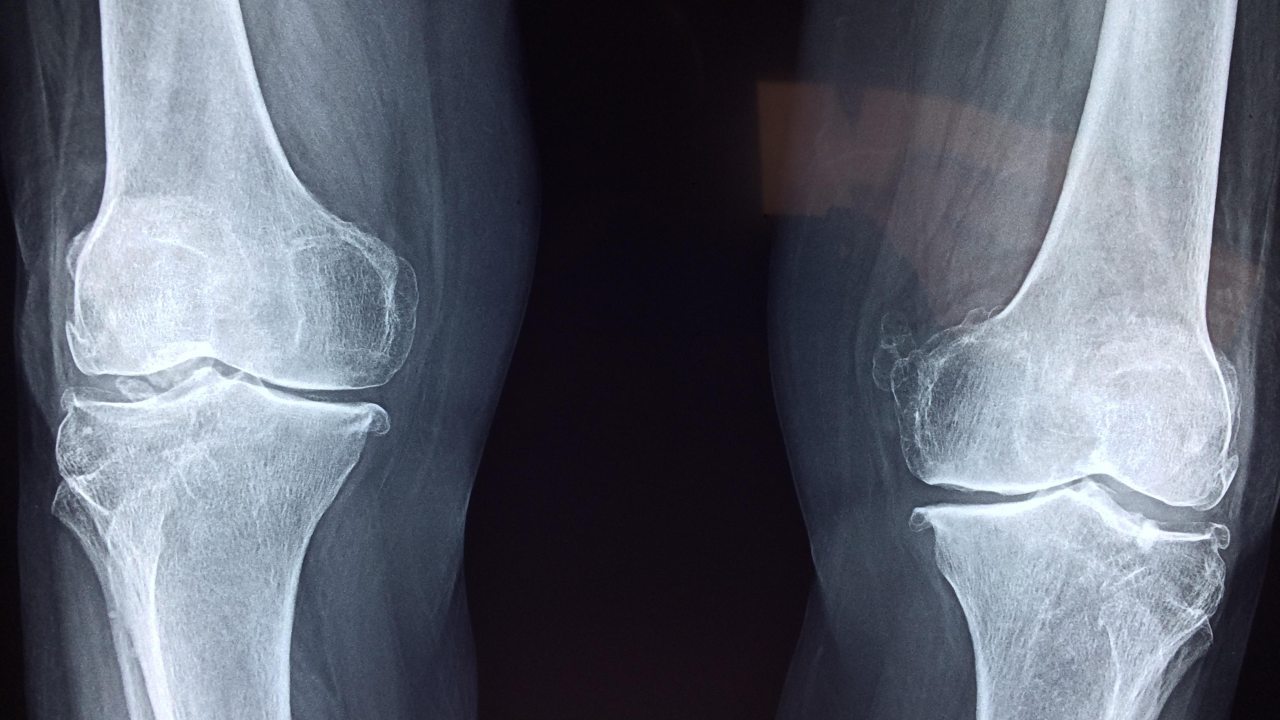

가장 흔한 증상은 통증이에요. 특히 무릎에 골관절염이 생기면 계단을 오르내릴 때 통증을 더 심하게 느낄 수 있습니다.

대부분 문진과 진찰로 어렵지 않게 진단할 수 있으며, 엑스레이 검사를 통해 확진합니다.